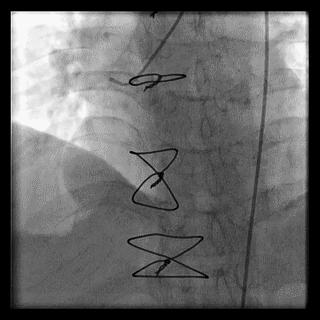

桡动脉迂曲在TRI中是一常见问题,约占3.8%~4.2%,桡动脉迂曲的部位在桡动脉近心端三分之一处,老年及女性患者的发生率要明显高于其他人群。根据桡动脉迂曲的形态可进一步将其细分“S”、“α”、“Ω”以及“Z”等多种类型,其中以“S”和“Ω”形迂曲最为常见,不同类型的桡动脉迂曲处理难度亦不相同,例如桡动脉“S”形迂曲的处理相对较为容易,其操作成功率要高于其它类型的桡动脉迂曲。

“S”

“α”

“Ω”